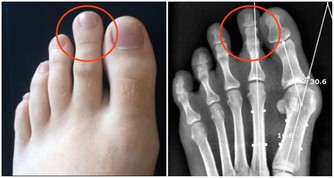

而喝酒臉紅正是因為體內缺乏將乙醛轉化為乙酸的酶,

導致乙醛在體內蓄積,損害肝臟功能,增加肝病風險,長期飲酒也會導致食道癌的發生。

美國《PlosMedicine》雜誌刊載了一篇名為《酒精性臉紅的反應:來自於飲酒關於食管癌未知的風險因素》的論文,美國國家酗酒與酒精中毒研究所和日本久里濱酒精過敏研究中心的研究人員的聯合研究發現,對於體內缺乏乙醛脫氫酶2或這種酶不能正常發揮作用的人群來說,患食道癌的風險隨酒精攝入量的增多而增大。